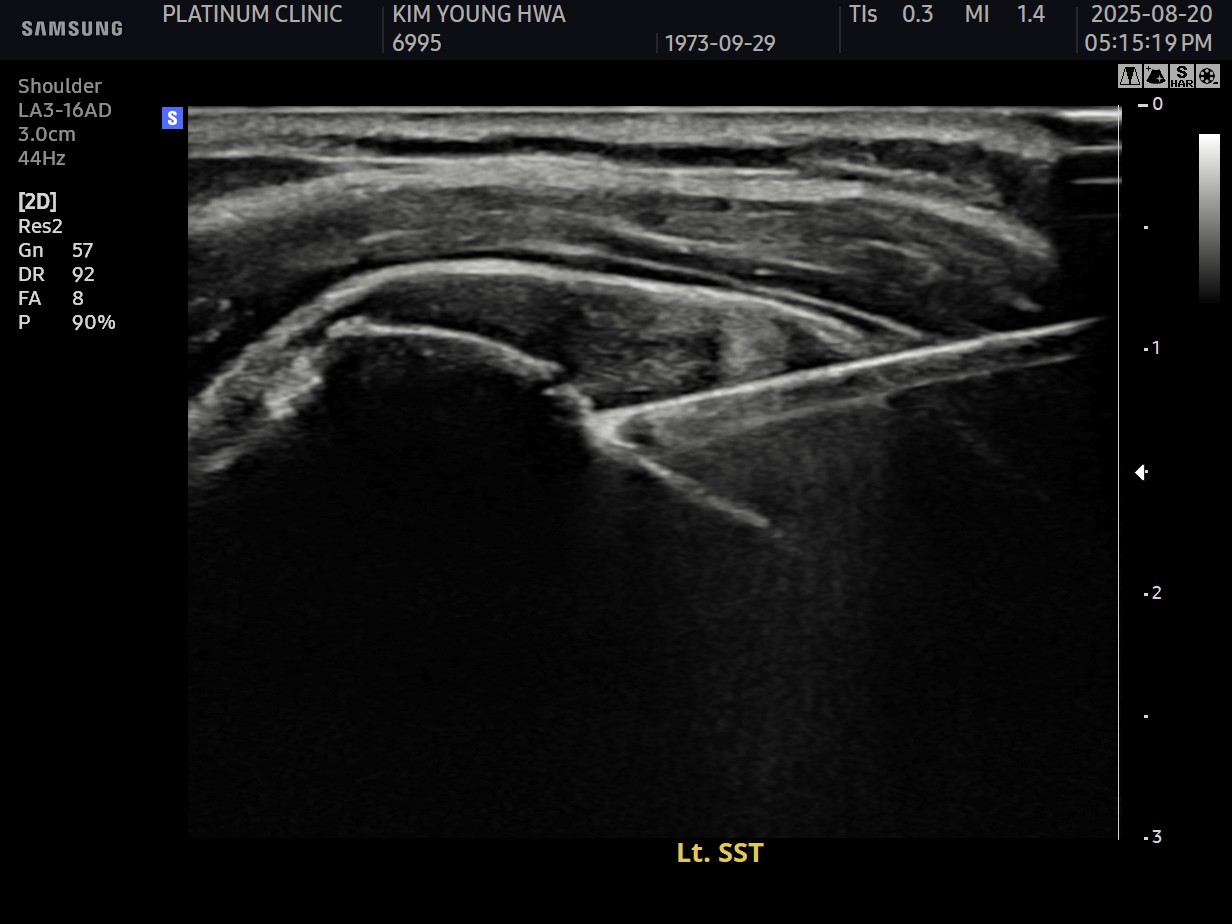

진단 결과:

- ✓관절면측 부분파열: 약 35%

- ✓근육 위축이나 지방 변성은 없음 (젊은 나이)

시술 과정

시술 시간: 약 35분

10주 후 초음파:

봉합 부위가 정상 인대처럼 하얗게 재생되어 있었습니다. 골수자극의 효과로 예상보다 빠른 재생이 확인되었습니다.

4개월 후: 벤치프레스 70kg 성공. 이전 무게의 약 80% 회복.

6개월 후: 이전 수준 완전 복귀.